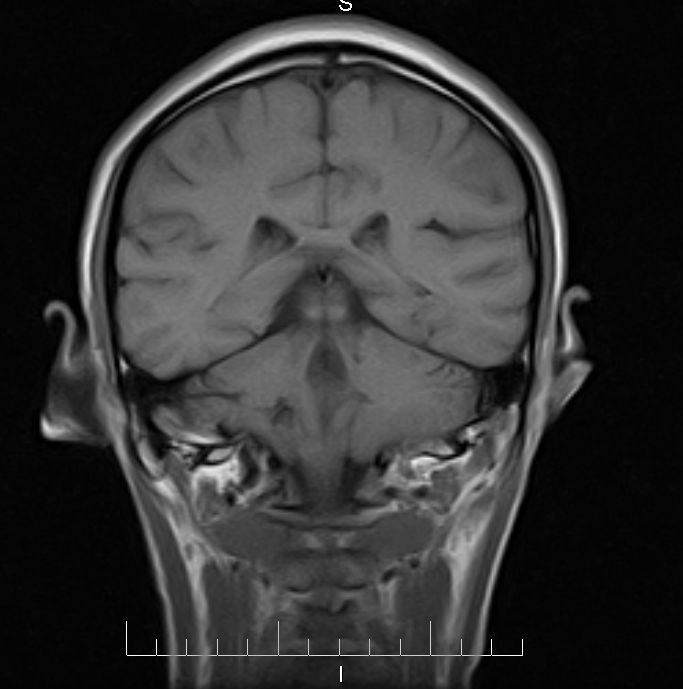

标题: MRI2379:30岁,男,癫痫10年,请各位看一下;CT示:左颞叶钙 [打印本页]

标题: MRI2379:30岁,男,癫痫10年,请各位看一下;CT示:左颞叶钙

左颞叶区见不规则点状混杂信号影

支持2楼 左颞叶区见不规则点状混杂信号影,考虑动静脉畸形。

考虑左侧颞叶脑血管畸形(avm)。----t1低等高混杂信号,t2等高信号周边较多流空血管影[冠状位明显],mra左侧大脑中动脉受压,远侧聚集.